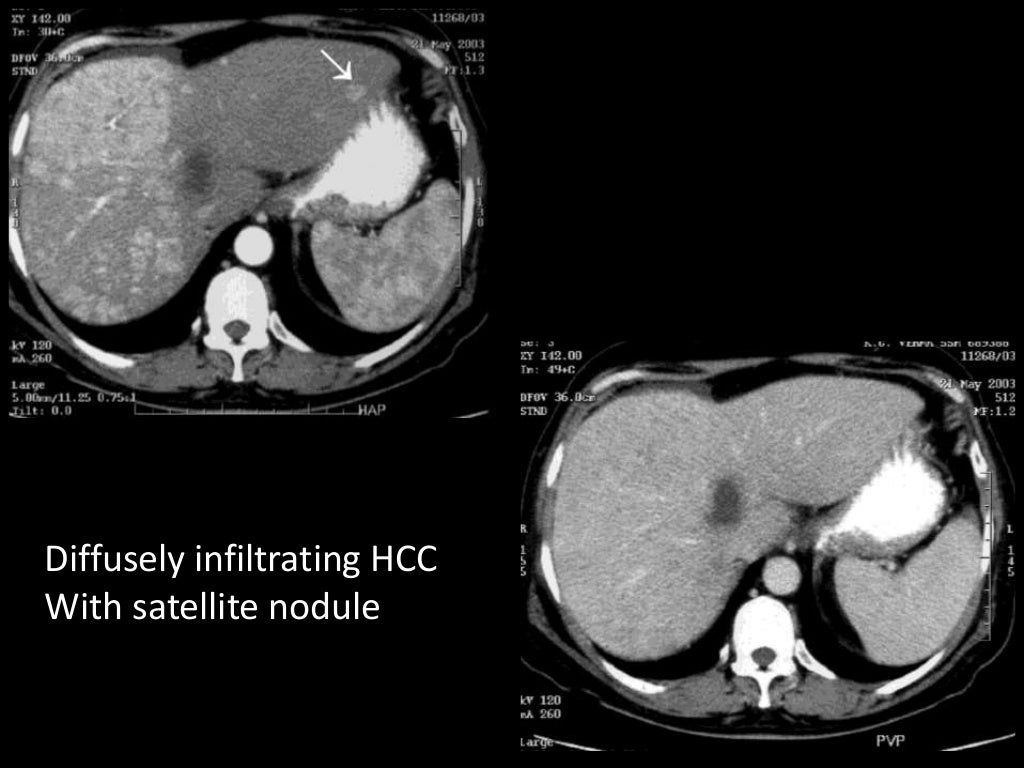

Imaging of Malignant Liver Lesions Malignant Medical Imaging Definition Imaging forms an essential part of cancer clinical protocols and is able to furnish morphological, structural, metabolic and. In contrast, tumors that stay localized and don't spread are called benign. A neoplasm is an abnormal growth of tissue that can be benign (noncancerous) or malignant (cancerous). A malignant tumor is a group of diseased cells defined by one of three. Malignant Medical Imaging Definition.

From www.slideshare.net

Imaging of Malignant Liver Lesions Malignant Medical Imaging Definition A malignant tumor is a group of diseased cells defined by one of three characteristics: Doctors use imaging tests to take pictures of the inside of your body. Benign tumors (noncancerous neoplasms) usually grow. In contrast, tumors that stay localized and don't spread are called benign. Radiologist yolanda bryce (right) and ultrasound supervisor van castor are part of a team. Malignant Medical Imaging Definition.

Imaging of Malignant Liver Lesions Malignant Medical Imaging Definition Imaging is able to spatially map key cancer features and tumor heterogeneity improving tumor diagnosis, characterization, and management. Imaging tests can be used to look for cancer, find out how far it has spread,. Uncontrolled growth, invasion and damage of healthy cells, or metastasizing (spreading) to. Doctors use imaging tests to help find and diagnose. Imaging forms an essential part. Malignant Medical Imaging Definition.